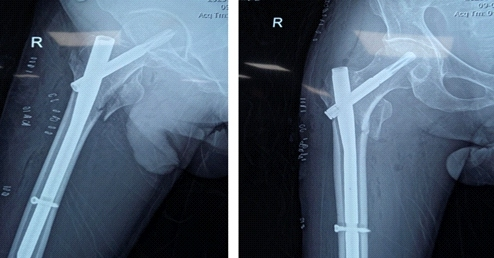

经过全面的医疗优化和多学科评估后,患者接受了闭合复位和近端股骨钉内固定手术。

术中出血量极少,血流动力学全程稳定。 术后远端脉搏持续未触及,足趾脉搏血氧饱和度无法记录,患肢进行性变冷、感觉丧失。